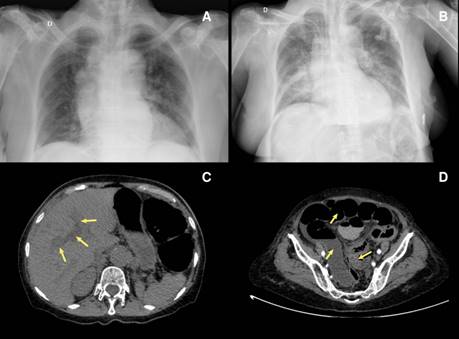

Upon admission, in the physical examination, she had a blood pressure of 143/91 mm Hg, a mean arterial pressure of 108 mm Hg, a heart rate of 74 BPM, a respiratory rate of 15 BPM, and temperature of 36.8°C. She presented a distended abdomen without signs of peritoneal irritation and no skin lesions. In the paraclinical findings there were 12,000x109 leukocytes/L, 80% neutrophils, hemoglobin of 9.4 g/dL, 517,000x109 platelets/L, 4.3 mmol/L potassium, 142 mmol/L sodium, 106 mmol/L chlorine, creatinine levels in 1.1 mg/dL, and ureic nitrogen of 43 mg/dL. The initial chest X-ray showed cardiomegaly without alveolar infiltrates (figure 1A).

Chest X-ray revealed multiple bilateral perihilar alveolar infiltrates. Abdomen contrast-enhanced computed tomography showed cholelithiasis, intra- and extrahepatic dilated bile ducts, marked distension of the intestinal loops, and bowel wall thickening with intestinal lumen obliteration at the sigmoid colon level (figure 1B-D). A septic shock of abdominal origin was considered. Blood cultures were taken. The patient initiated invasive ventilatory support and treatment with intravenous injection of 4.5 g piperacillin/tazobactam every six hours, plus 500 mg metronidazole every eight hours. Vasopressor therapy was added with norepinephrine and vasopressin. Persistence of the distended abdomen was associated with voiding of fecaloid material through an orogastric tube. After 24 hours of antibiotic management, the patient presented multiple asystolic episodes without response to resuscitation and died.